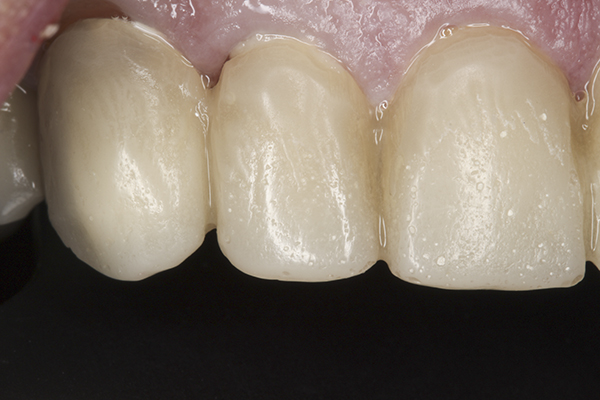

(39.) Postoperative anterior, close-up view.

Figure 39

(40.) Postoperative left anterior, close-up view.

Figure 40